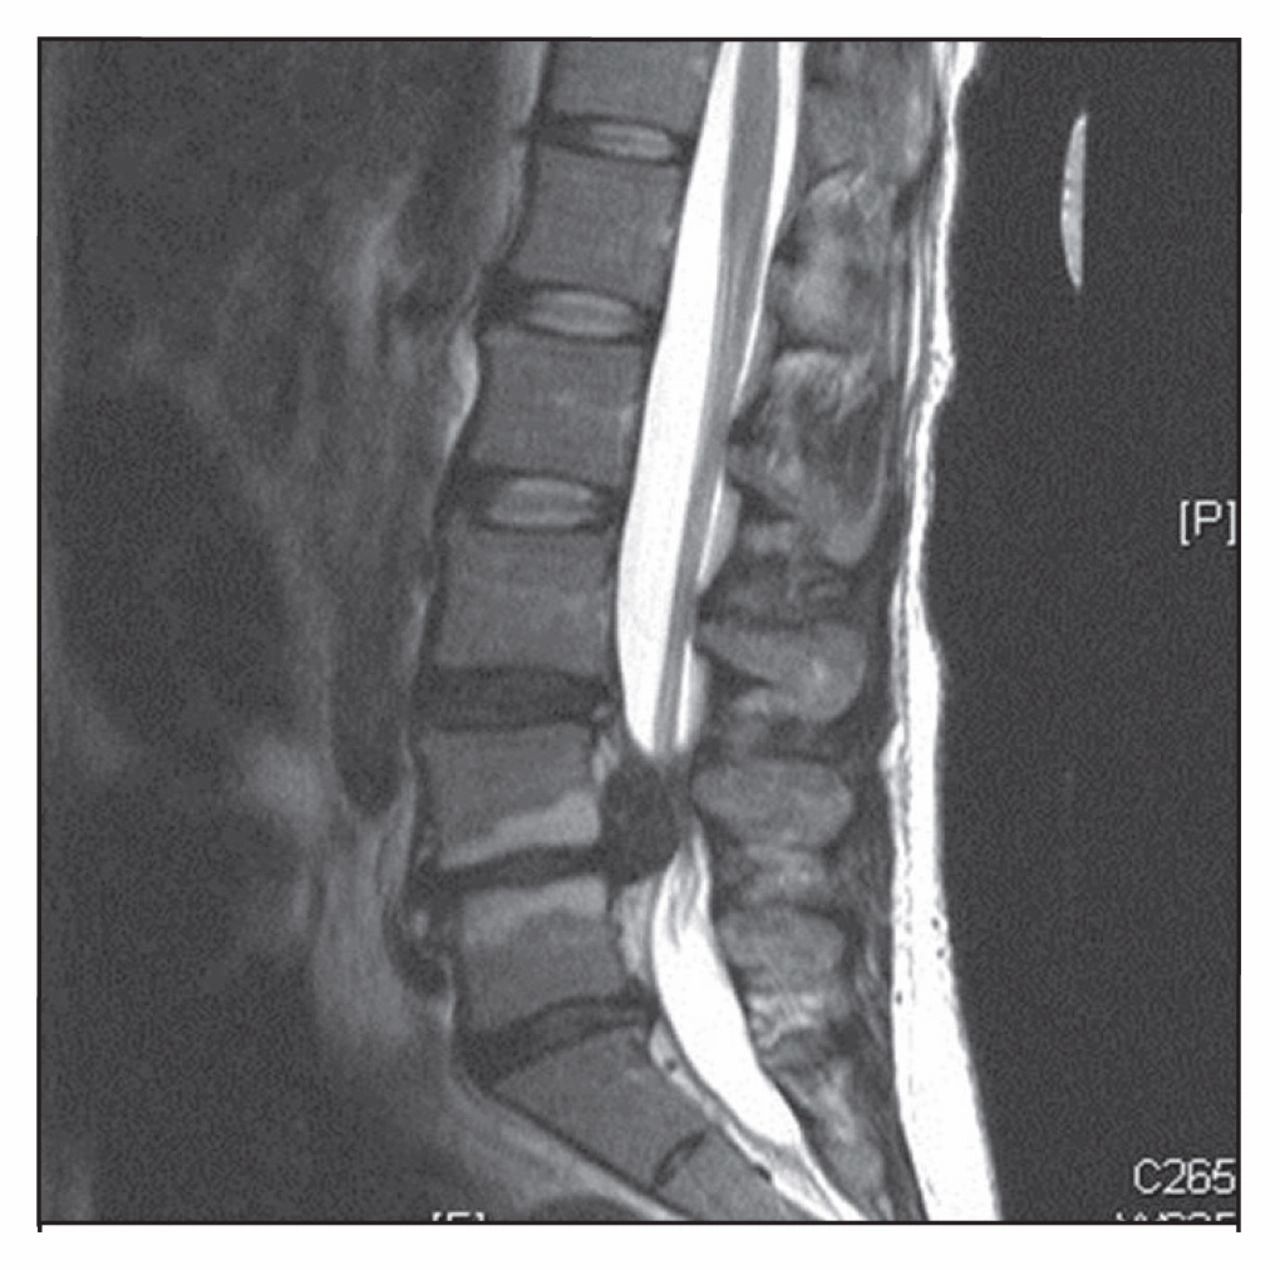

4. Cauda equina syndrome

The cauda equina is the bundle of nerve roots at the bottom of the spinal cord that supplies the legs, the bladder, the bowel, and the perineum. When those nerves are compressed acutely, usually by a large herniated disc, the result is a true surgical emergency. Without prompt decompression, the deficits can become permanent.

The “red flag” symptoms are well known to anyone who treats back pain: urinary retention or incontinence, bowel incontinence, “saddle anesthesia” (numbness in the area of the body that would touch a saddle), bilateral leg weakness, and severe back or radicular pain. Sexual dysfunction can also feature.

The misdiagnosis pattern is that a patient with severe back pain is treated as a routine mechanical back pain case, with analgesia and discharge. The red flag questions are not asked. The neurological examination, including a check for saddle anesthesia and a post-void bladder scan, is not done. The window for surgical decompression, generally within 24 to 48 hours of acute symptoms, is missed. The deficits become permanent.